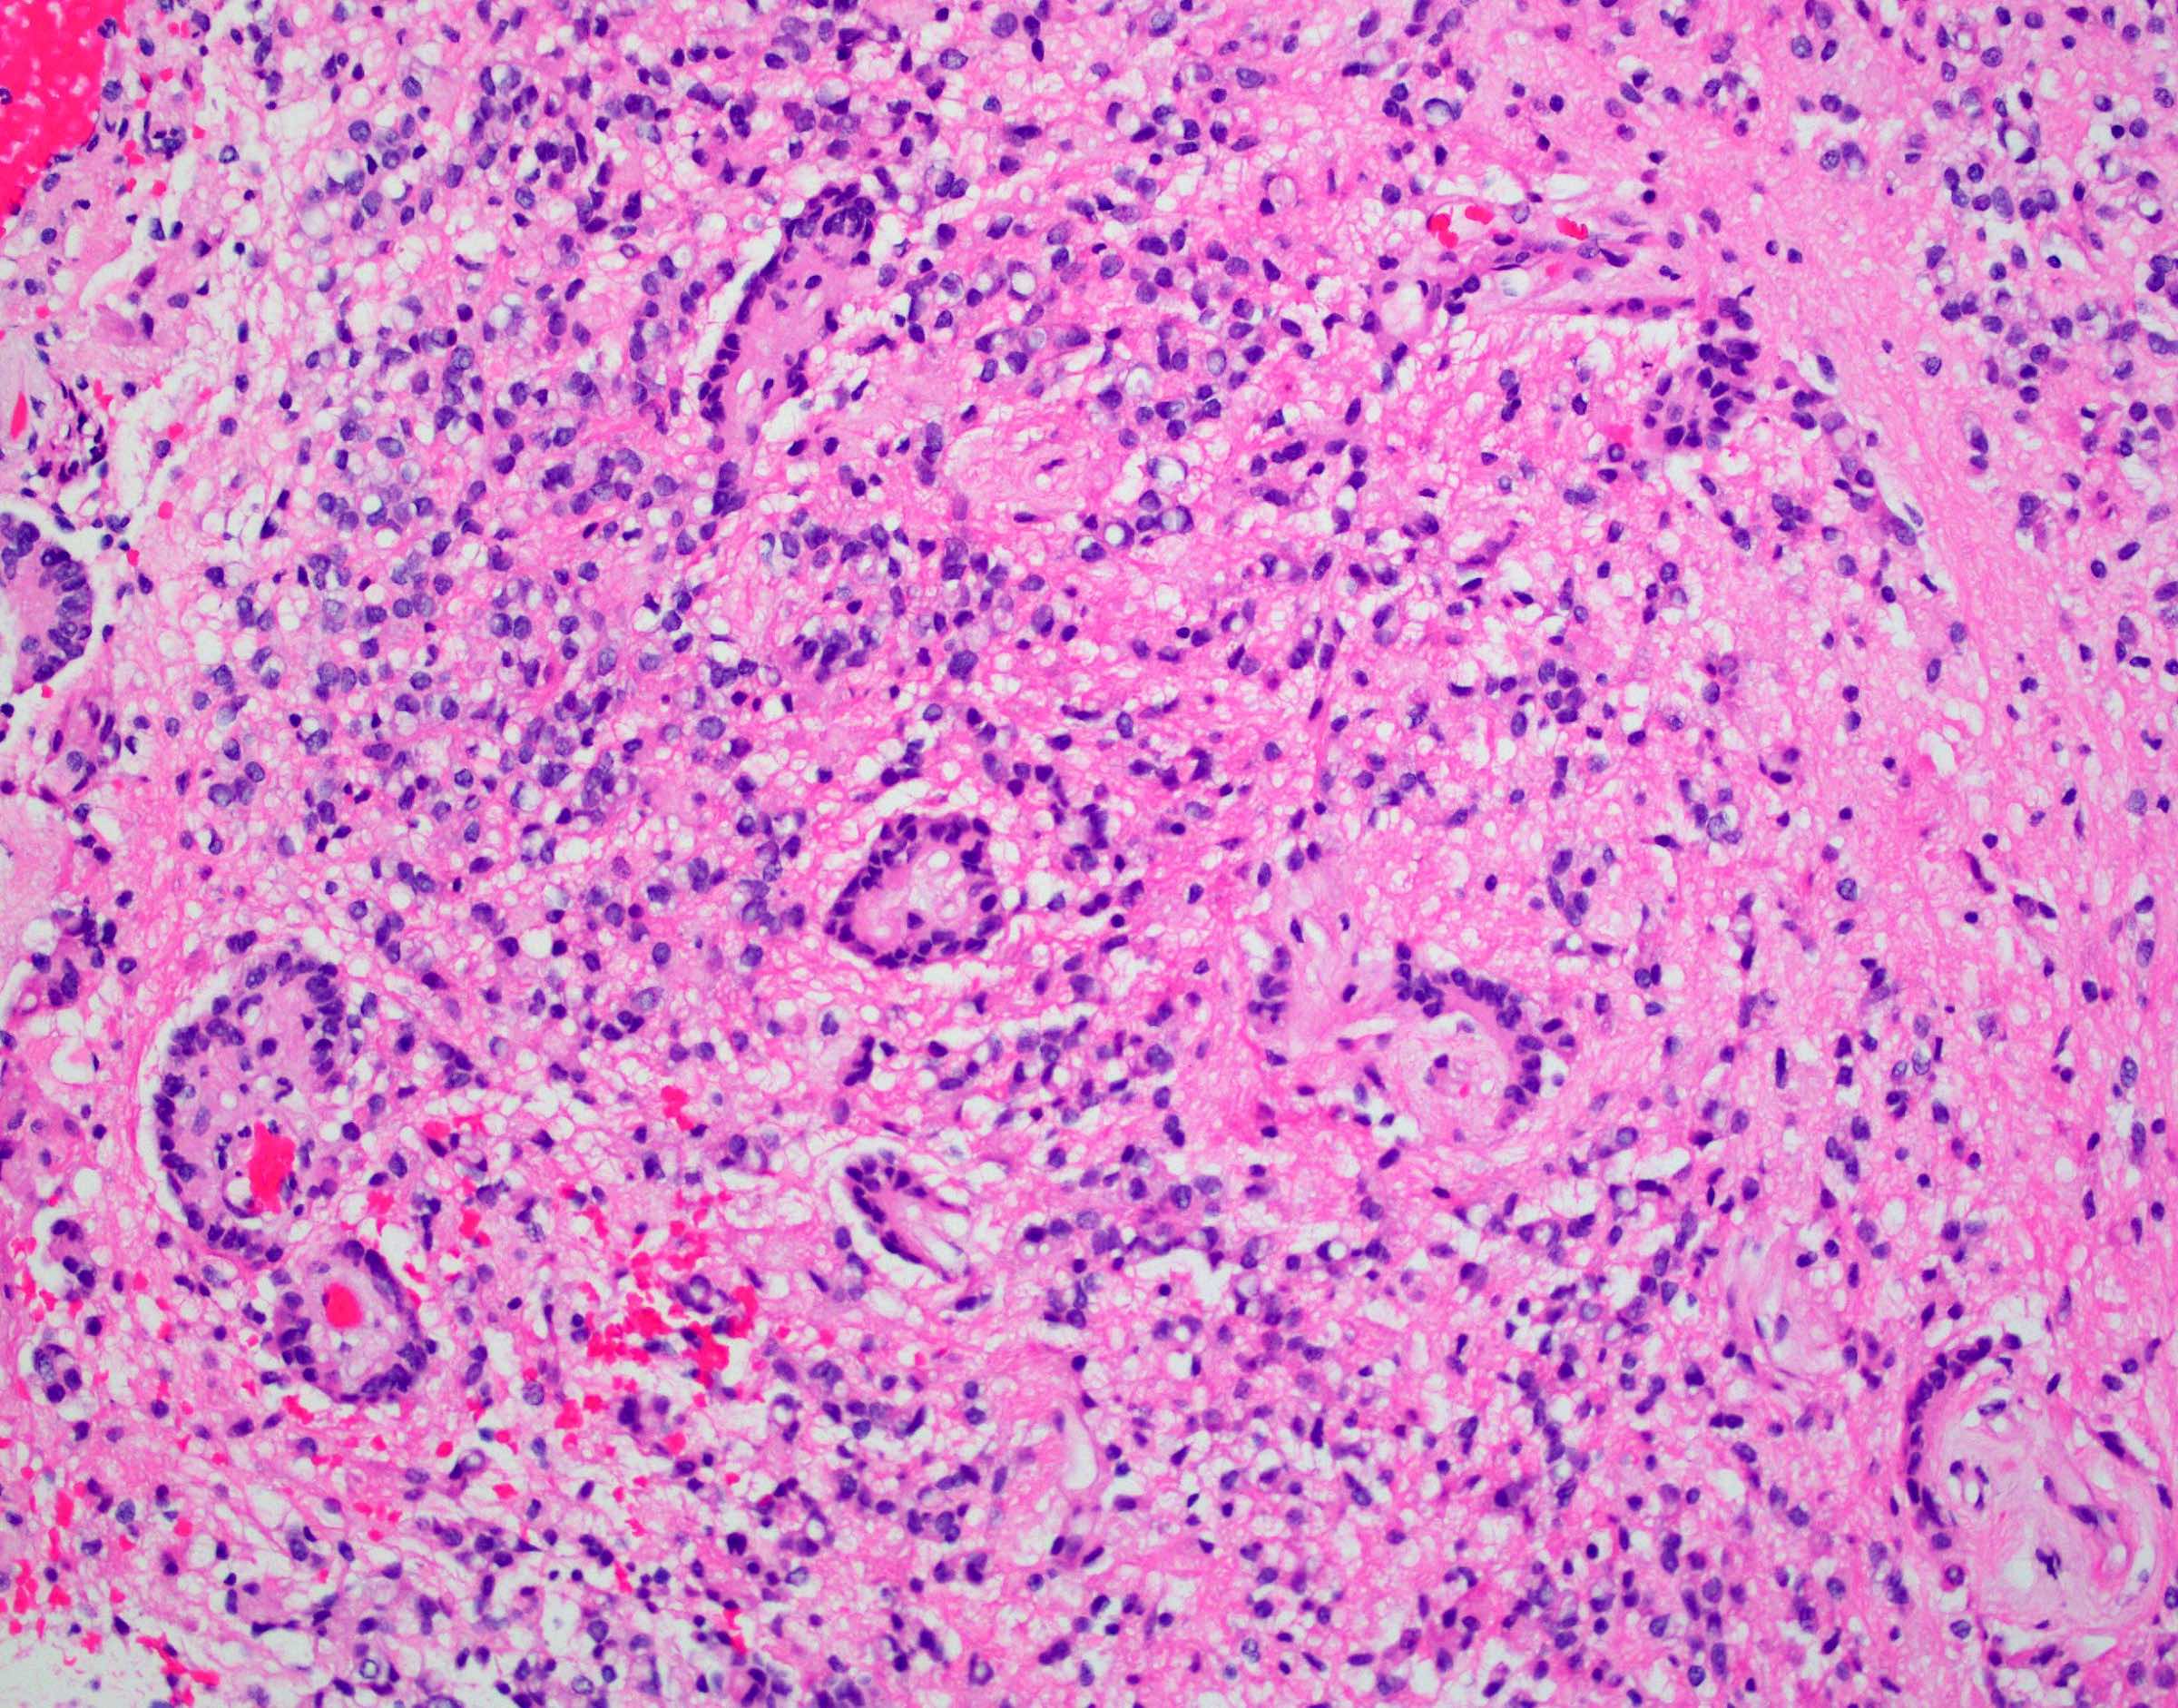

Microscopic (histologic) description

- Perivascular pseudorosettes, true ependymal rosettes, lumina and fibrillar areas

- Can have nonpalisading necrosis, areas of cystic or myxoid degeneration, calcifications, degenerative atypia, neuronal differentiation and rarely metaplastic elements

- Morphologic subtypes have no clinicopathological significance and include papillary, clear cell and tanycytic

Microscopic (histologic) images